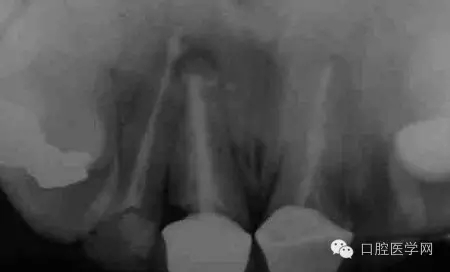

根尖切除術(shù)操作全過程

圖1 X線顯示上11根尖息肉陰影